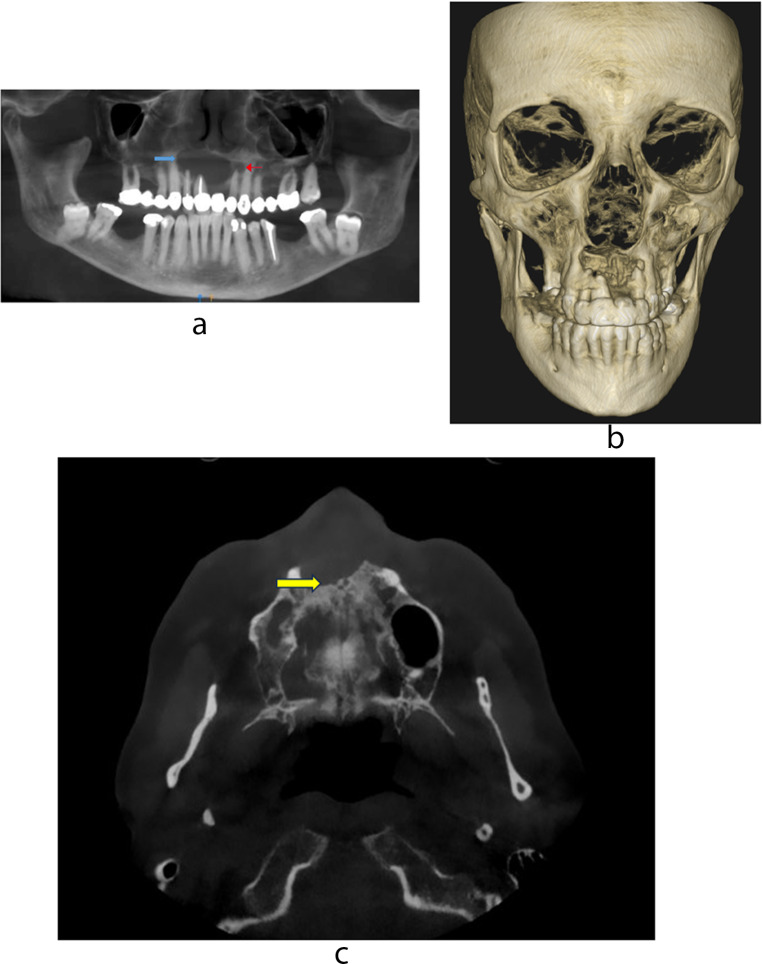

Methods: A 58-year-old female presented with isolated erythematous dry skin lesions and a radiolucent lesion of the anterior maxilla. Microscopic examination of the enucleation specimen revealed a periapical cyst with large collections of atypical cells with grooved folded nuclei with eosinophils consistent with LCH. Immunohistochemistry (IHC) was performed to confirm the diagnosis. BRAF mutation status was evaluated with the BRAF p. V600E antibody and the automated real-time PCR-based Idylla™ assay, capable of qualitative detection of 5 mutations in codon 600 of the BRAF gene.